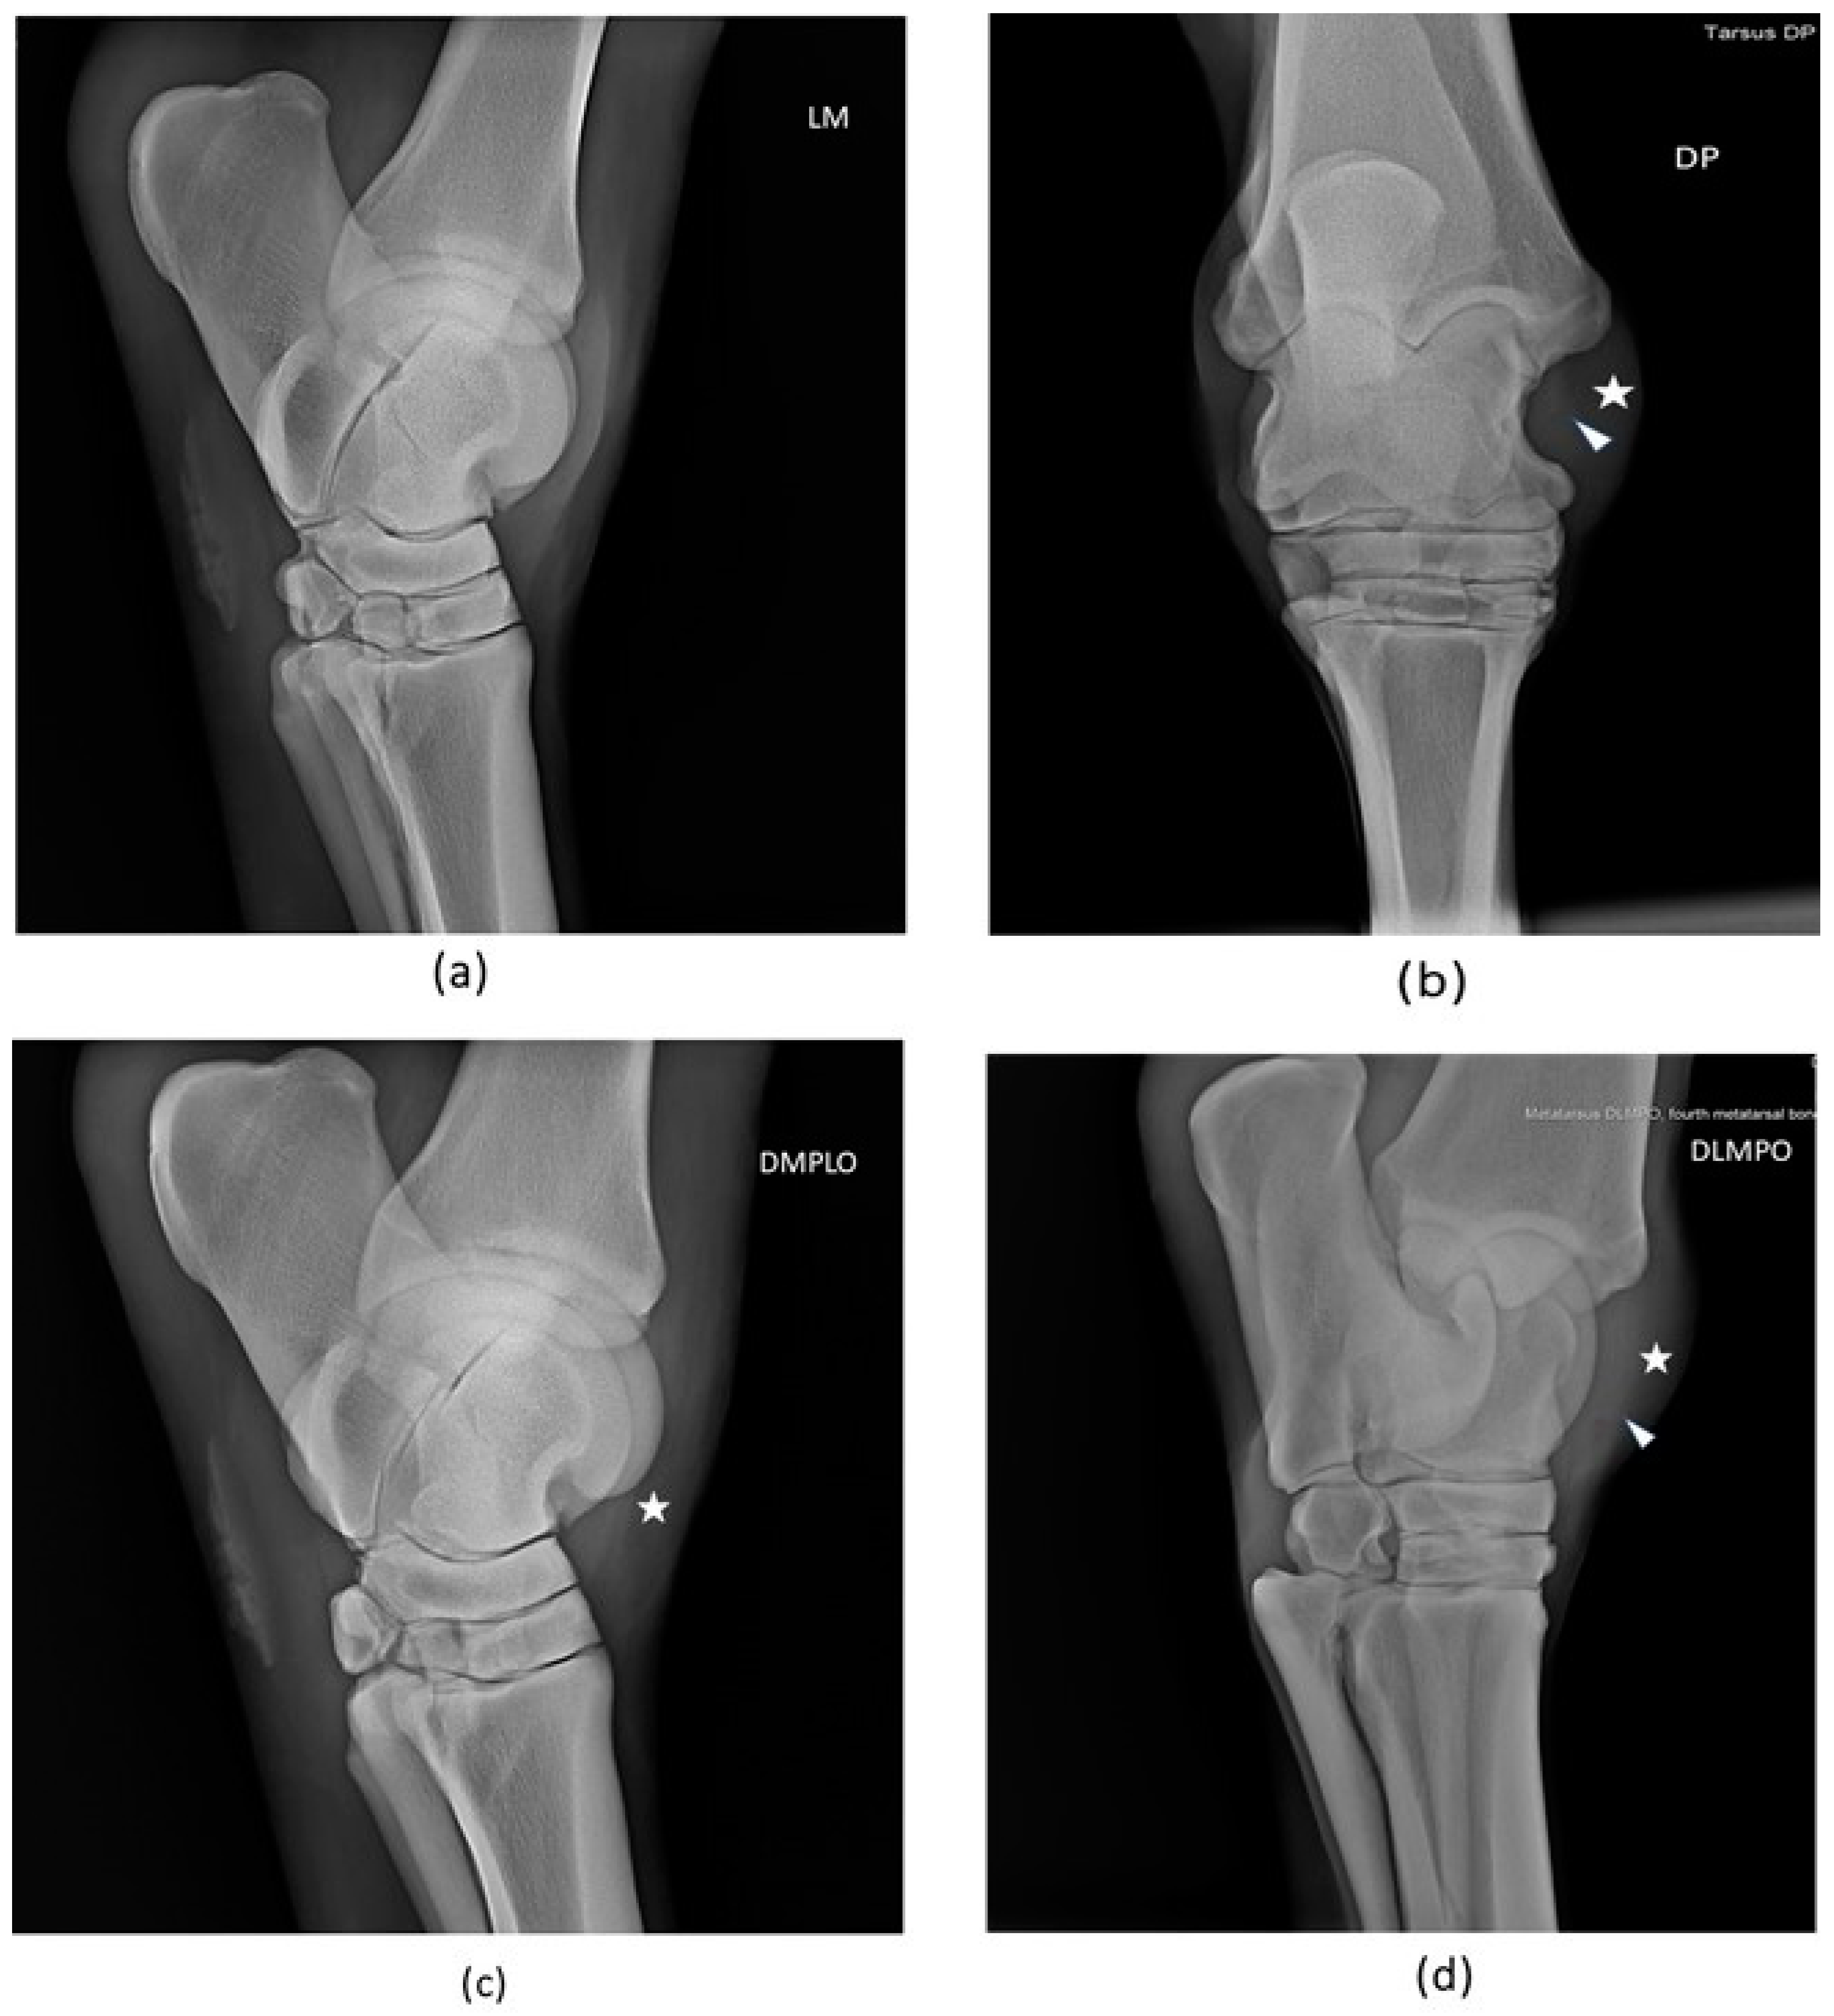

2.4.1. Radiological examination

3.1.1. Radiological examination